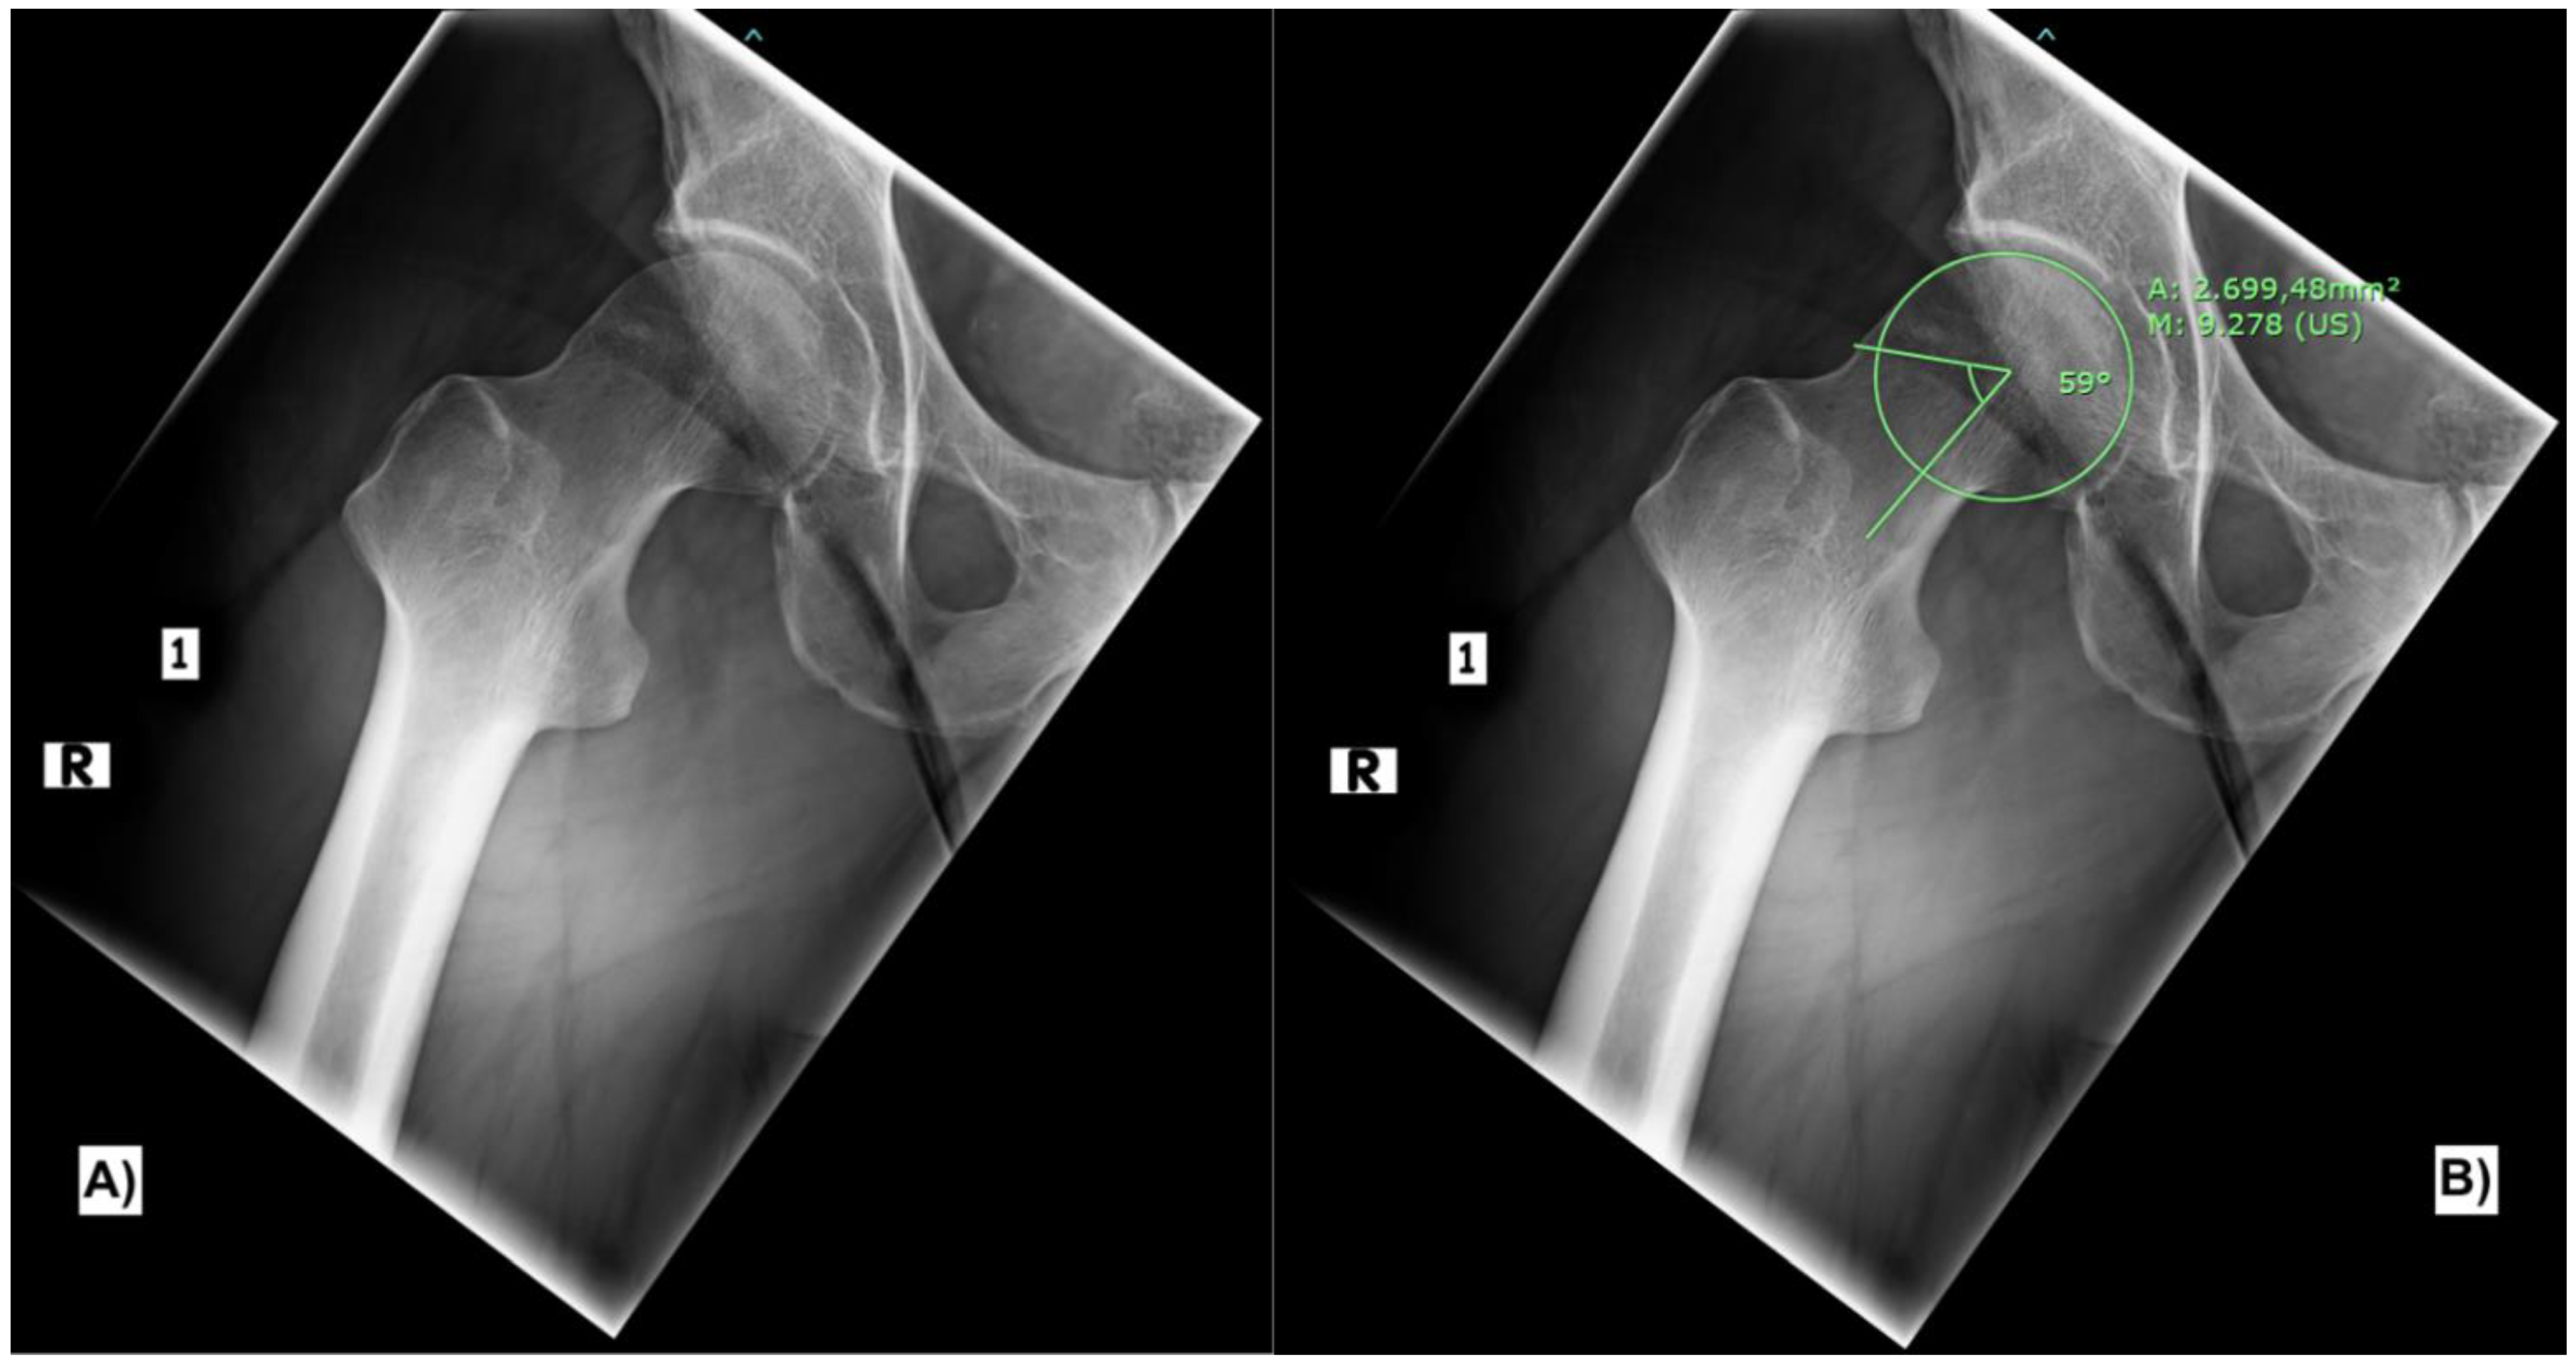

(PDF) PartialThickness Tears of the Gluteus Medius Rationale and What Is A Partial Thickness Tear Of Gluteus Medius Tendon This review article summarizes the anatomy, clinical presentation, and treatment options for gluteus medius and minimus tears,. Tears in the gluteus medius and minimus tendons, often misdiagnosed as trochanteric bursitis, have recently emerged as an important cause of recalcitrant greater. Common symptoms of gluteal tears. It may hurt more after sitting for lengthy periods or after exercising. Find out how. What Is A Partial Thickness Tear Of Gluteus Medius Tendon.